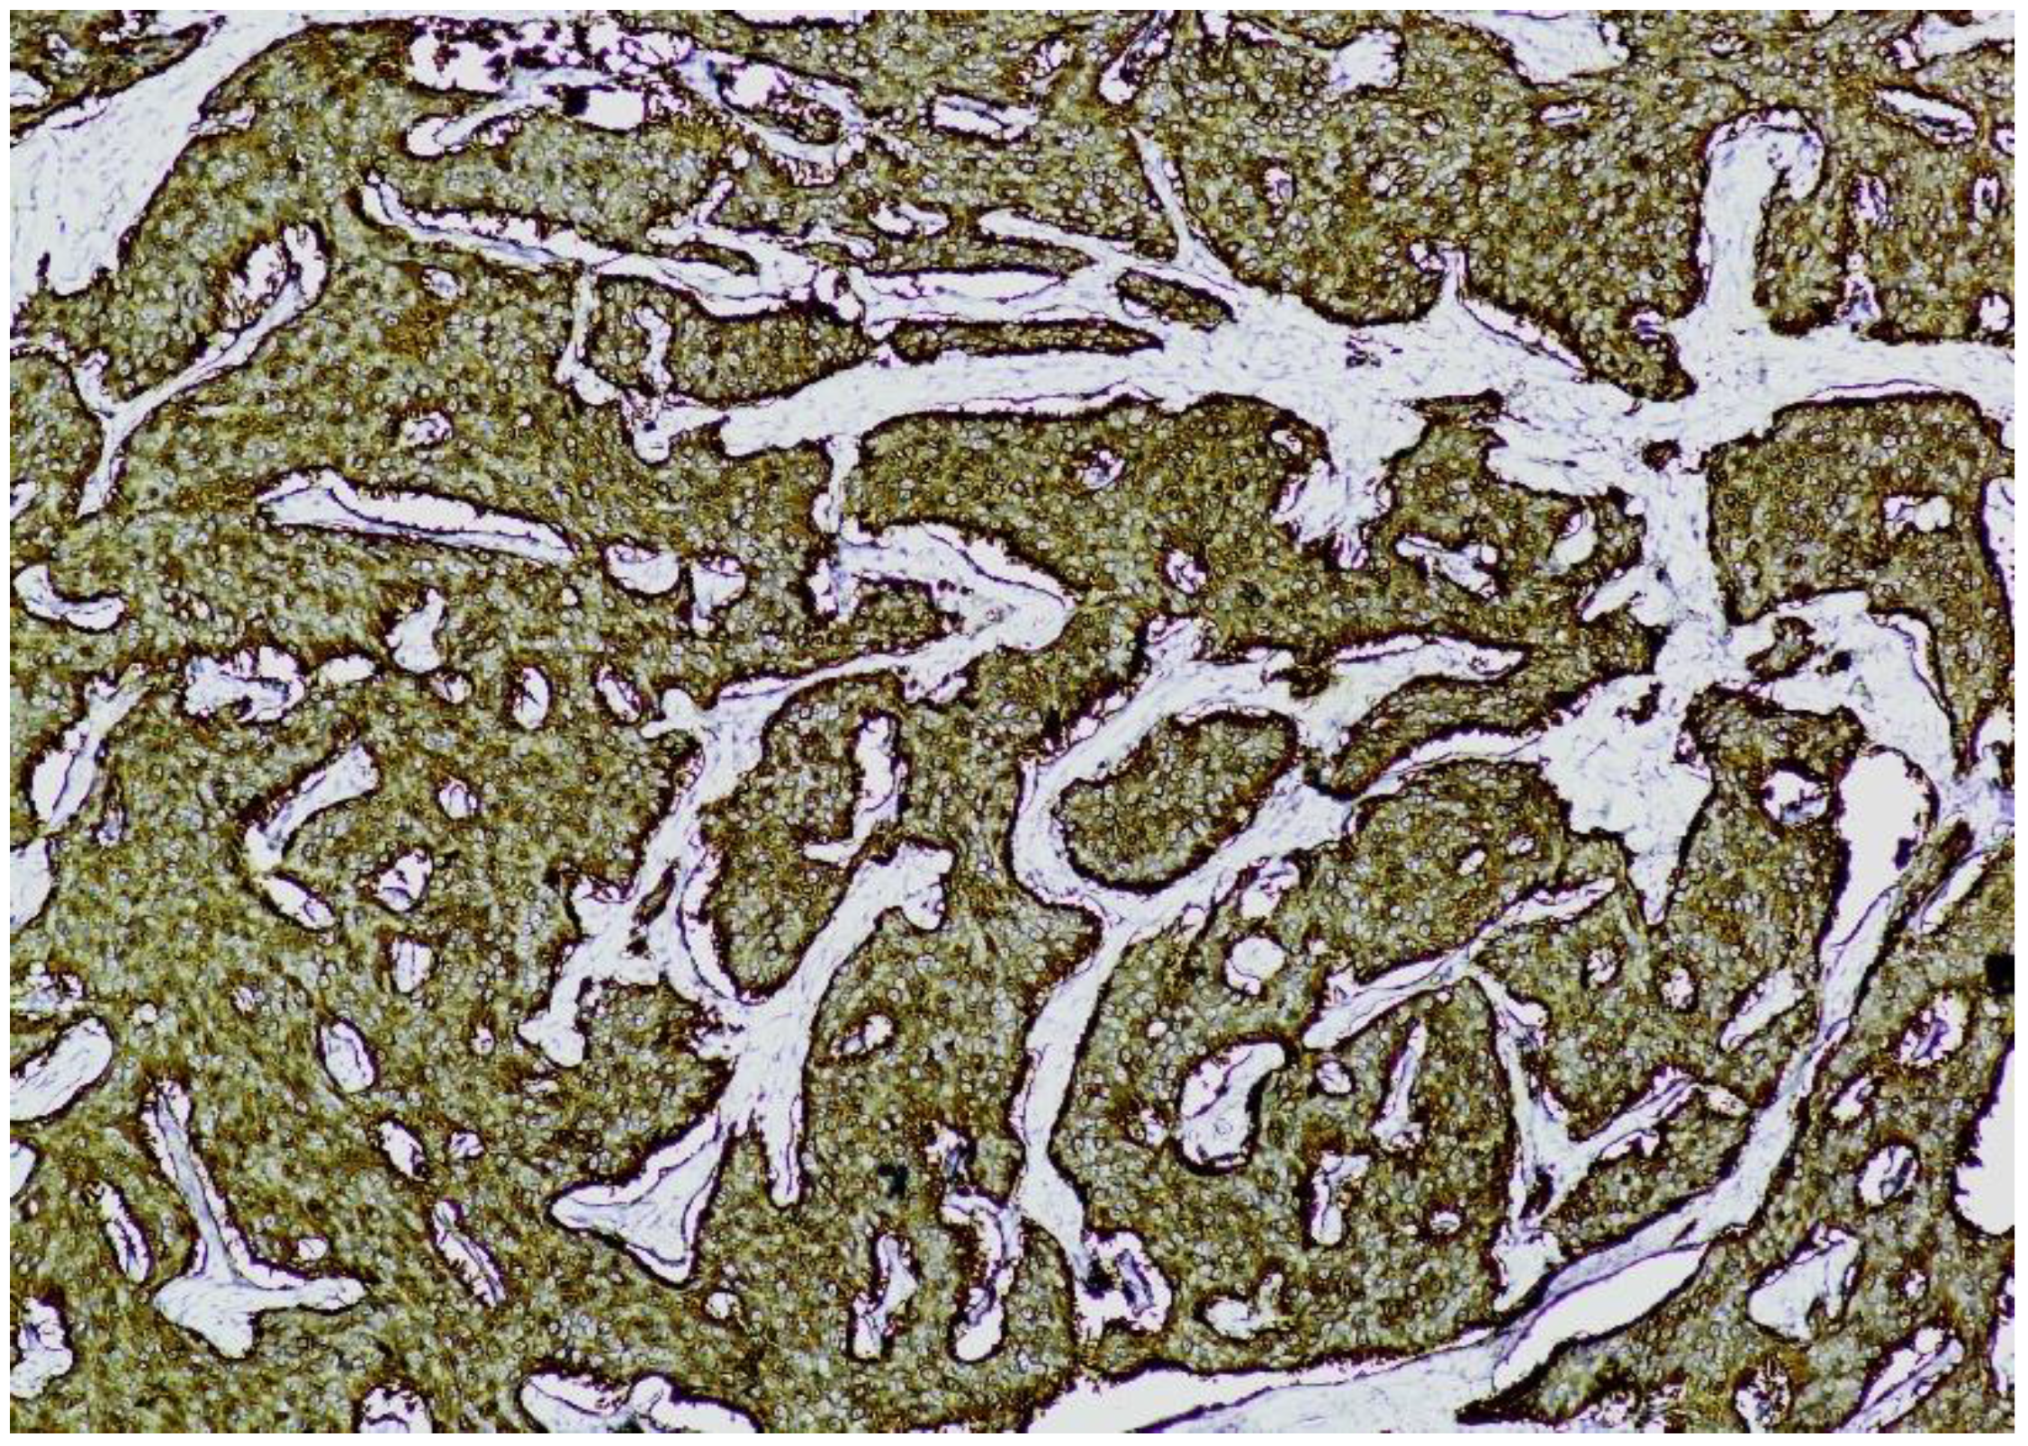

Immunohistochemistry (IHC) showed diffuse and strong positivity for chromogranin A and CD56, with focal weak staining for synaptophysin, supporting neuroendocrine differentiation (Figure 5, Figure 6, Figure 7 and Figure 8).

Figure 7. CD56 immunostaining (×100). The image shows nests of well-differentiated neuroendocrine tumor cells exhibiting diffuse and strong membranous CD56 positivity, consistent with neuroendocrine phenotype.